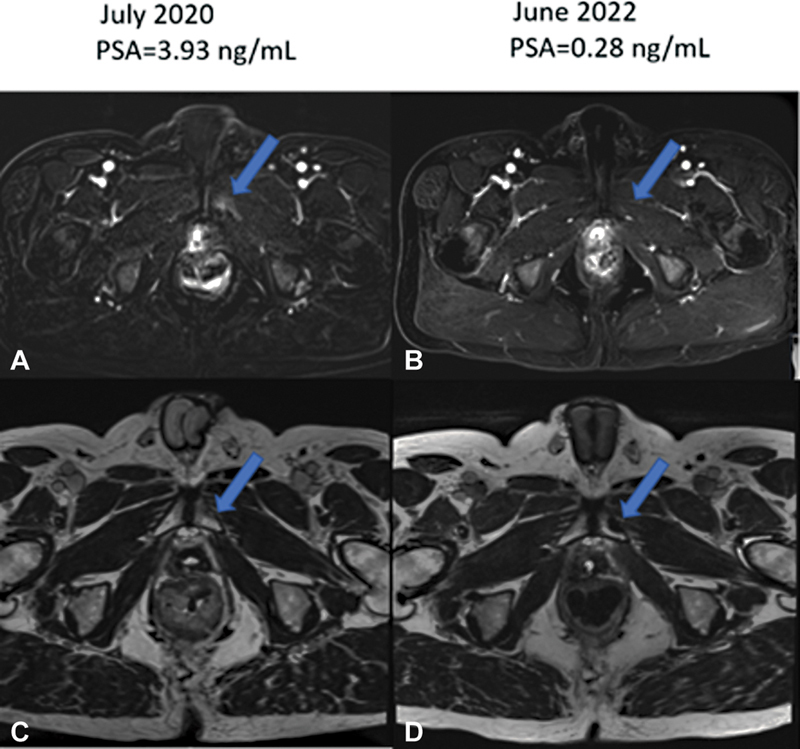

Skeletal metastases due to prostate cancer (PCa) are more commonly osteoblastic than osteolytic. In the rarer cases of osteolytic skeletal metastasis of PCa, transition to osteoblastic phenotype occurs following treatment, which indicates successful healing. In this report, we present a case of spontaneous osteolytic to osteoblastic evolution of PCa skeletal metastasis without treatment in a patient with recurrence of PCa. Our patient is a 59-year-old male who had a robotic radical prostatectomy in July 2014 for a T2c adenocarcinoma of the prostate gland (Gleason score = 4 + 3). He had adjuvant pelvic radiotherapy in January 2015 due to prostate-specific antigen (PSA) persistence. PSA began to rise in October 2015. An 18 F-fluciclovine positron emission tomography/computed tomography (PET/CT) scan obtained in June 2017 at a PSA of 0.5 ng/mL was negative. Repeat 18 F-fluciclovine PET/CT of February 2020 at PSA of 3.72 ng/mL showed prostate bed recurrence and a nonavid osteolytic left inferior pubic ramus lesion. 18F radiohybrid prostate-specific membrane antigen ( 18 F-rhPSMA) PET/CT scan of August 2020 performed as part of an ongoing clinical trial confirmed local prostate bed recurrence with a low-grade radiotracer uptake in the osteolytic left inferior pubic ramus bone lesion. Without salvage therapy, 18 F-fluciclovine PET/CT of October 2020 and March 2022 shows progressive sclerosis in the left pubic ramus lesion. An osteolytic to osteoblastic transition of a bone lesion as shown in this patient calls for a rethink in our understanding of untreated PCa skeletal metastasis progression. This case provides novel insight into the understanding of the temporal evolution of skeletal metastasis and calls for further research.